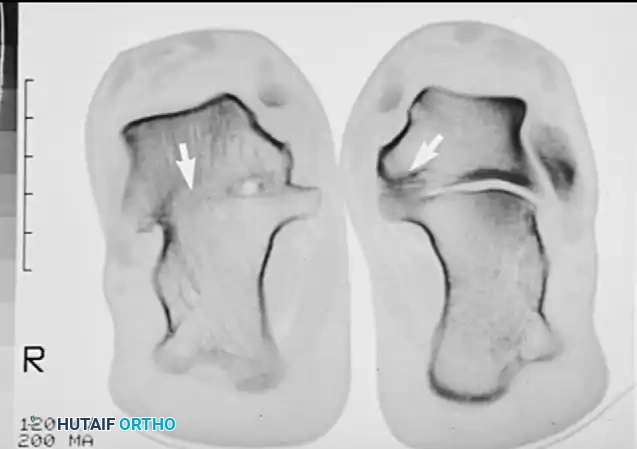

Advanced Imaging: Computed Tomography (CT)

CT is the undisputed gold standard for the diagnosis and surgical planning of talocalcaneal coalitions.

Surgical Warning: Instructions to the radiography technician must be explicit. The primary cuts of the CT must be perpendicular to the posterior and middle facets of the subtalar joint (the semicoronal plane) at 3-mm increments. Standard axial or sagittal cuts may miss a subtle middle facet coalition.

Semicoronal CT scan clearly demonstrating a middle facet talocalcaneal coalition.

CT not only confirms the diagnosis but defines the exact location, size, and margins of the coalition. It is critical for assessing the condition of the remaining subtalar articulations at the posterior facet.

Semicoronal CT scan demonstrating bilateral middle facet coalitions. Bilateral involvement is common and must always be ruled out.